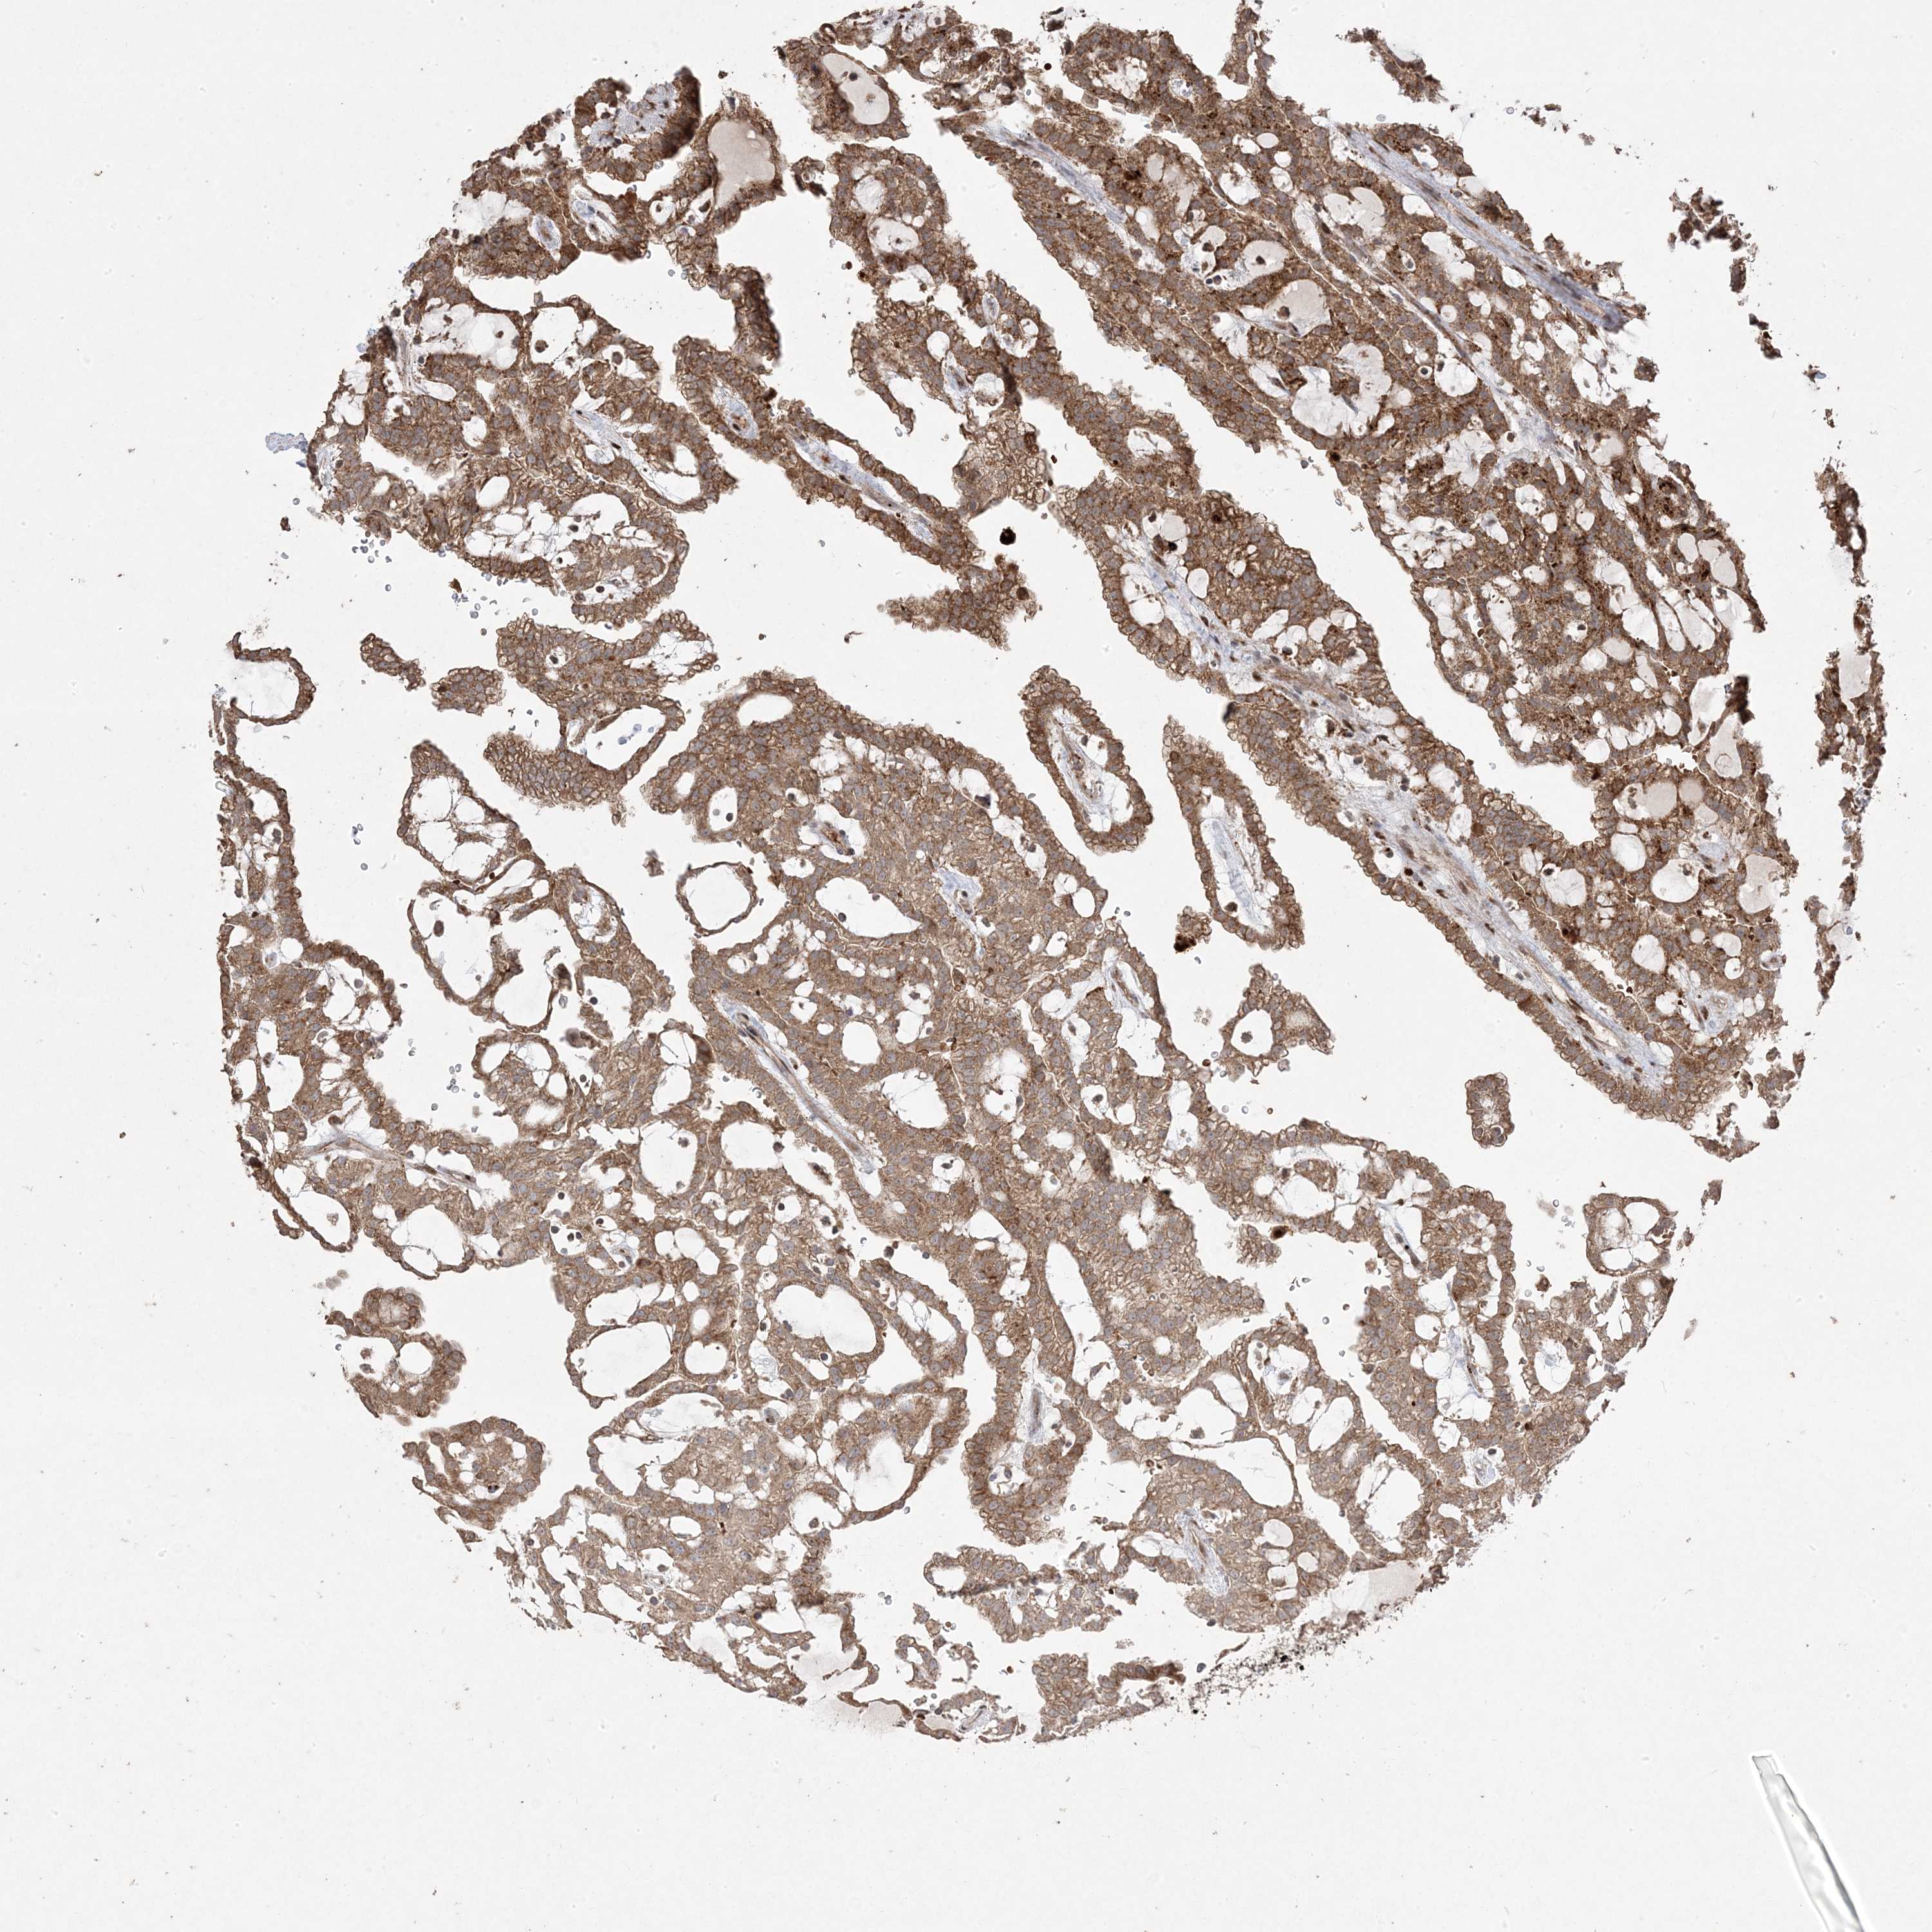

CANCER RENAL CANCER Show tissue menu

KICH TCGA KIRC TCGA KIRC VALIDATION KIRP TCGA PROTEIN RCC CPTAC PROTEIN EXPRESSION

TCGA RNA samplesi

RNA-seq data is reported as average FPKM (number Fragments Per Kilobase of exon per Million reads), generated by the The Cancer Genome Atlas (TCGA) .

Normal distribution across the dataset is visualized with box plots, shown as median and 25th and 75th percentiles. Points are displayed as outliers if they are above or below 1.5 times the interquartile range. FPKM values of the individual samples are presented next to the box plot.

Average pTPM 10.2

Number of samples 521